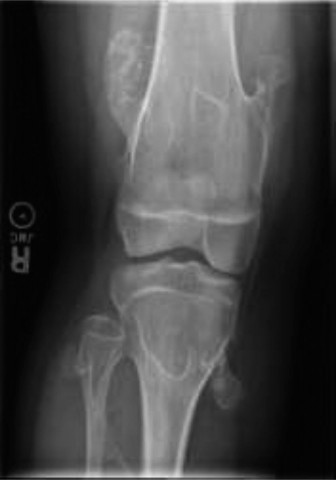

CASE 36 A 12-year-old boy is brought to your clinic for evaluation after being …